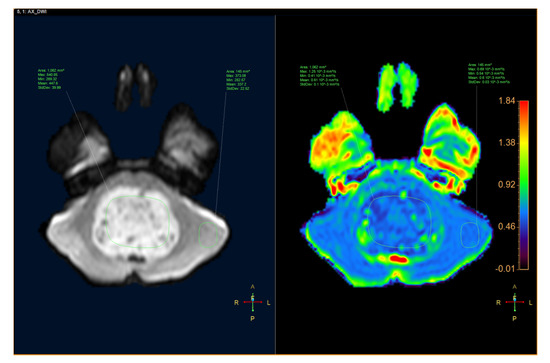

ADC was quantified by defining the region of interest (ROI) for the tumor and the parenchyma on the ADC map with MR Diffusion tool available in Philips Intellispace Portal, version 11 (Philips, Best, The Netherlands). ADC will provide the following parameters: maximum ADC (ADCmax), minimum ADC (ADCmin), mean ADC (ADCmean), and standard deviation ADC (ADCsd). The following additional parameters were also assessed: the ratio of tumor ADCmax to parenchyma ADCmax (rADCmax), the ratio of tumor ADCmin to parenchyma ADCmin (rADCmin), the ratio of tumor ADCmean to parenchyma ADCmean (rADCmean), and the ratio of tumor ADCsd to parenchyma ADCsd (rADCsd) (Figure 1 and Figure 2).

Figure 2.

A 10-year-old male patient had a tumor located in the pons, which was diagnosed as a diffuse glioma. (Left) Axial DWI image. (Right) ADC map.